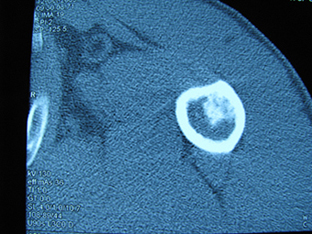

标题: X6404B:肱骨骨质破坏(CT片) [打印本页]

标题: X6404B:肱骨骨质破坏(CT片)

男,50岁,左肩部轻微疼痛,活动不便5个月就诊,近十天加重,无红肿热,间断理疗治疗无好转,既往5个月前左肩轻微拉伤史

骨巨?动脉瘤样骨囊肿?

内生软骨瘤。

内生软骨瘤。

内生软骨瘤?-----------

年纪大了,先要排除转移瘤。

髓腔内软组织肿块并斑片状钙化,考虑高分化软骨肉瘤可能性大。

考虑骨巨或动脉瘤样骨囊肿。

内生软骨瘤可能性大,期待结果。

孤立性骨囊肿。

内生软骨瘤可能性大

其内可见钙化,考虑软骨源性肿瘤,内生软骨瘤可能

但由于年龄较大,恶性软骨肉瘤待排

肱骨头内巨大软组织肿块并斑片状钙化,内生软骨瘤?骨巨细胞瘤?软骨粘液样纤维瘤?期待结果!

髓腔内软组织肿块并斑片状钙化,考虑高分化软骨肉瘤可能性大。

内生软骨瘤可能性大

肱骨头内巨大软组织肿块并斑片状钙化,内生软骨瘤?骨巨细胞瘤?软骨粘液样纤维瘤?期待结果

考虑内生软骨瘤?骨巨细胞瘤?

内生软骨瘤?骨巨细胞瘤?

先要排除转移瘤。